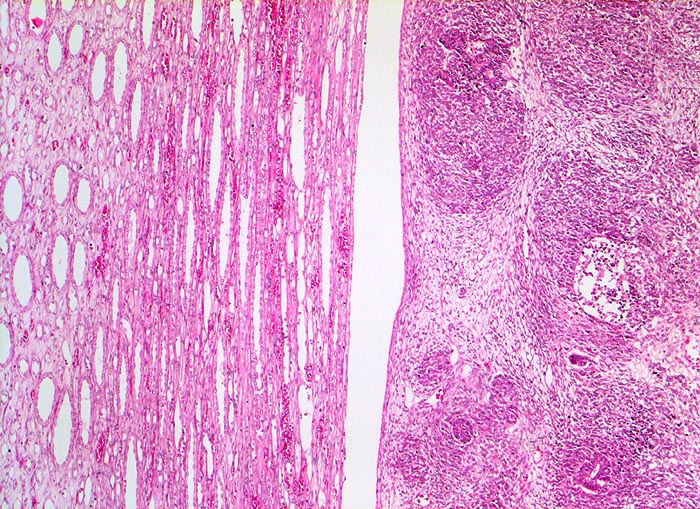

PathoPic ID 5179 - Wilms-Tumor

Wilms-Tumor

maligner Tumor

Niere

Paidopathologie

Das Nierenmark (links) wird durch den expansiv wachsenden scharf begrenzten Tumor (rechts) lediglich

komprimiert, nicht aber infiltriert.

Graubrauner scharf begrenzter weicher Tumor mit fokalen Nekrosen und Einblutungen.

Palpabler Tumor im linken Hemiabdomen. Makrohämaturieepisode.

Histologie

Vergrösserung

50

Alter

1

männlich